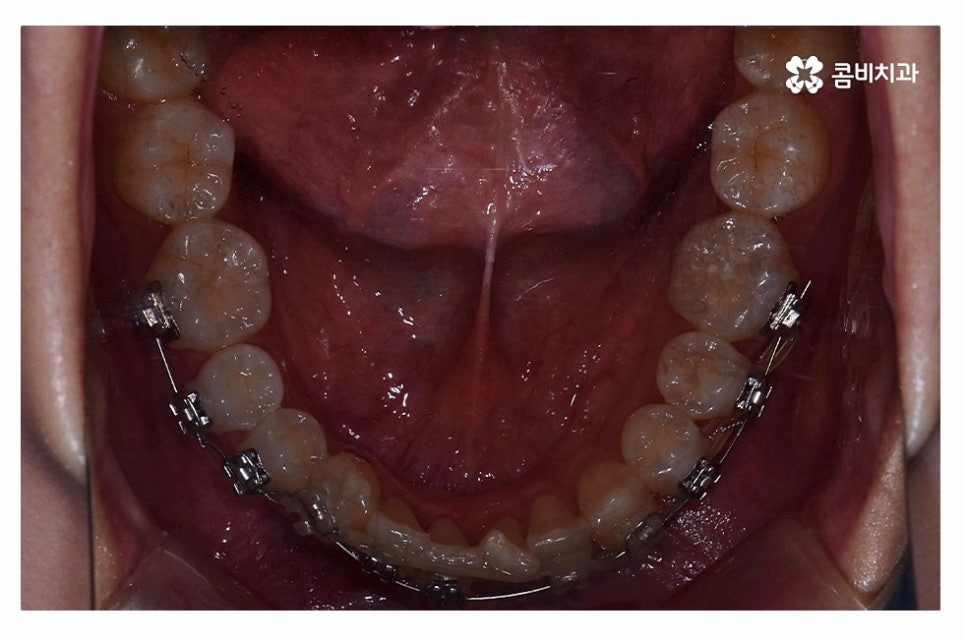

오늘 보여드릴 사례도 덧니교정이 비발치로 진행이 된 사례이며

치아의 이동 공간과 치아 상태, 골격, 얼굴형 등을

종합적으로 판단할 때 비발치로도 진행이 가능했던 사례라고 할 수 있어요.

교정 장치의 선택에 있어서는 다양한 교정 장치의 선택이 가능한데

심미성이 강조된 설측교정부터 콤비교정,

위 환자분의 사례처럼 클리피씨교정이 보편적으로 많이 활용되고 있는데요.

클리피씨교정은 치아의 이동이 일반 장치에 비해 상대적으로

빠르기 때문에 치료 기간이 단축될 수 있으며

통증의 감소, 내원 횟수를 줄일 수 있다는 장점 등이 있어요.